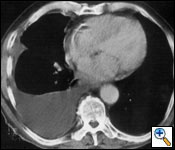

Radiological evaluation is essential to determine if a patient with MPM has potentially resectable disease. Posteroanterior and lateral chest roentgenogram (Figure 1), computerized tomography (CT scan) of the chest and upper abdomen (Figure 2), and magnetic resonance imaging (MRI) of chest have been the most widely used modalities. CT scan provides an estimate of tumor burden and extent of tumor both locally and distantly. MRI can supplement the CT scan for detection of tumor extension into the mediastinum or the abdomen. More recently, positron emission tomography (Figure 3) has been used to determine if a patient has early resectable disease based on no evidence of contralateral disease or distant metastasis. Early results are promising [6].